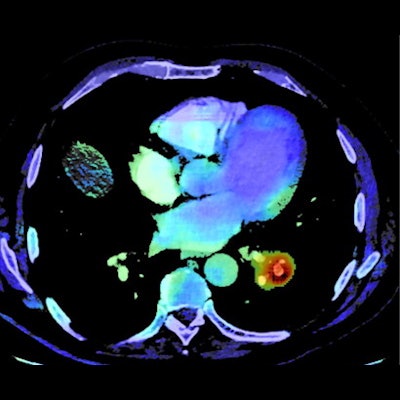

Example of an output provided by the AI algorithm (AIDOC Medical) to detect pulmonary embolism (PE). A: 64-year-old man presented with spontaneous unilateral pain in the lower limb, increased with palpation, and unilateral edema. The revised simplified Geneva score was 3 and the D-dimer dosage was positive. A contrast-enhanced CT pulmonary angiogram (CTPA) demonstrated a PE in the left lower limb (blue arrow). B: On the same cross-section, the AI algorithm highlighted the same location of the suspected PE through a color-encoded map. All figures courtesy of Dr. Alexandre Ben Cheikh and colleagues and European Radiology.

Example of an output provided by the AI algorithm (AIDOC Medical) to detect pulmonary embolism (PE). A: 64-year-old man presented with spontaneous unilateral pain in the lower limb, increased with palpation, and unilateral edema. The revised simplified Geneva score was 3 and the D-dimer dosage was positive. A contrast-enhanced CT pulmonary angiogram (CTPA) demonstrated a PE in the left lower limb (blue arrow). B: On the same cross-section, the AI algorithm highlighted the same location of the suspected PE through a color-encoded map. All figures courtesy of Dr. Alexandre Ben Cheikh and colleagues and European Radiology."Instead of replacing radiologists, AI for PE detection appears to be a safety net in emergency radiology practice due to high sensitivity and [negative predictive value], thereby increasing the self-confidence of radiologists," the authors wrote.